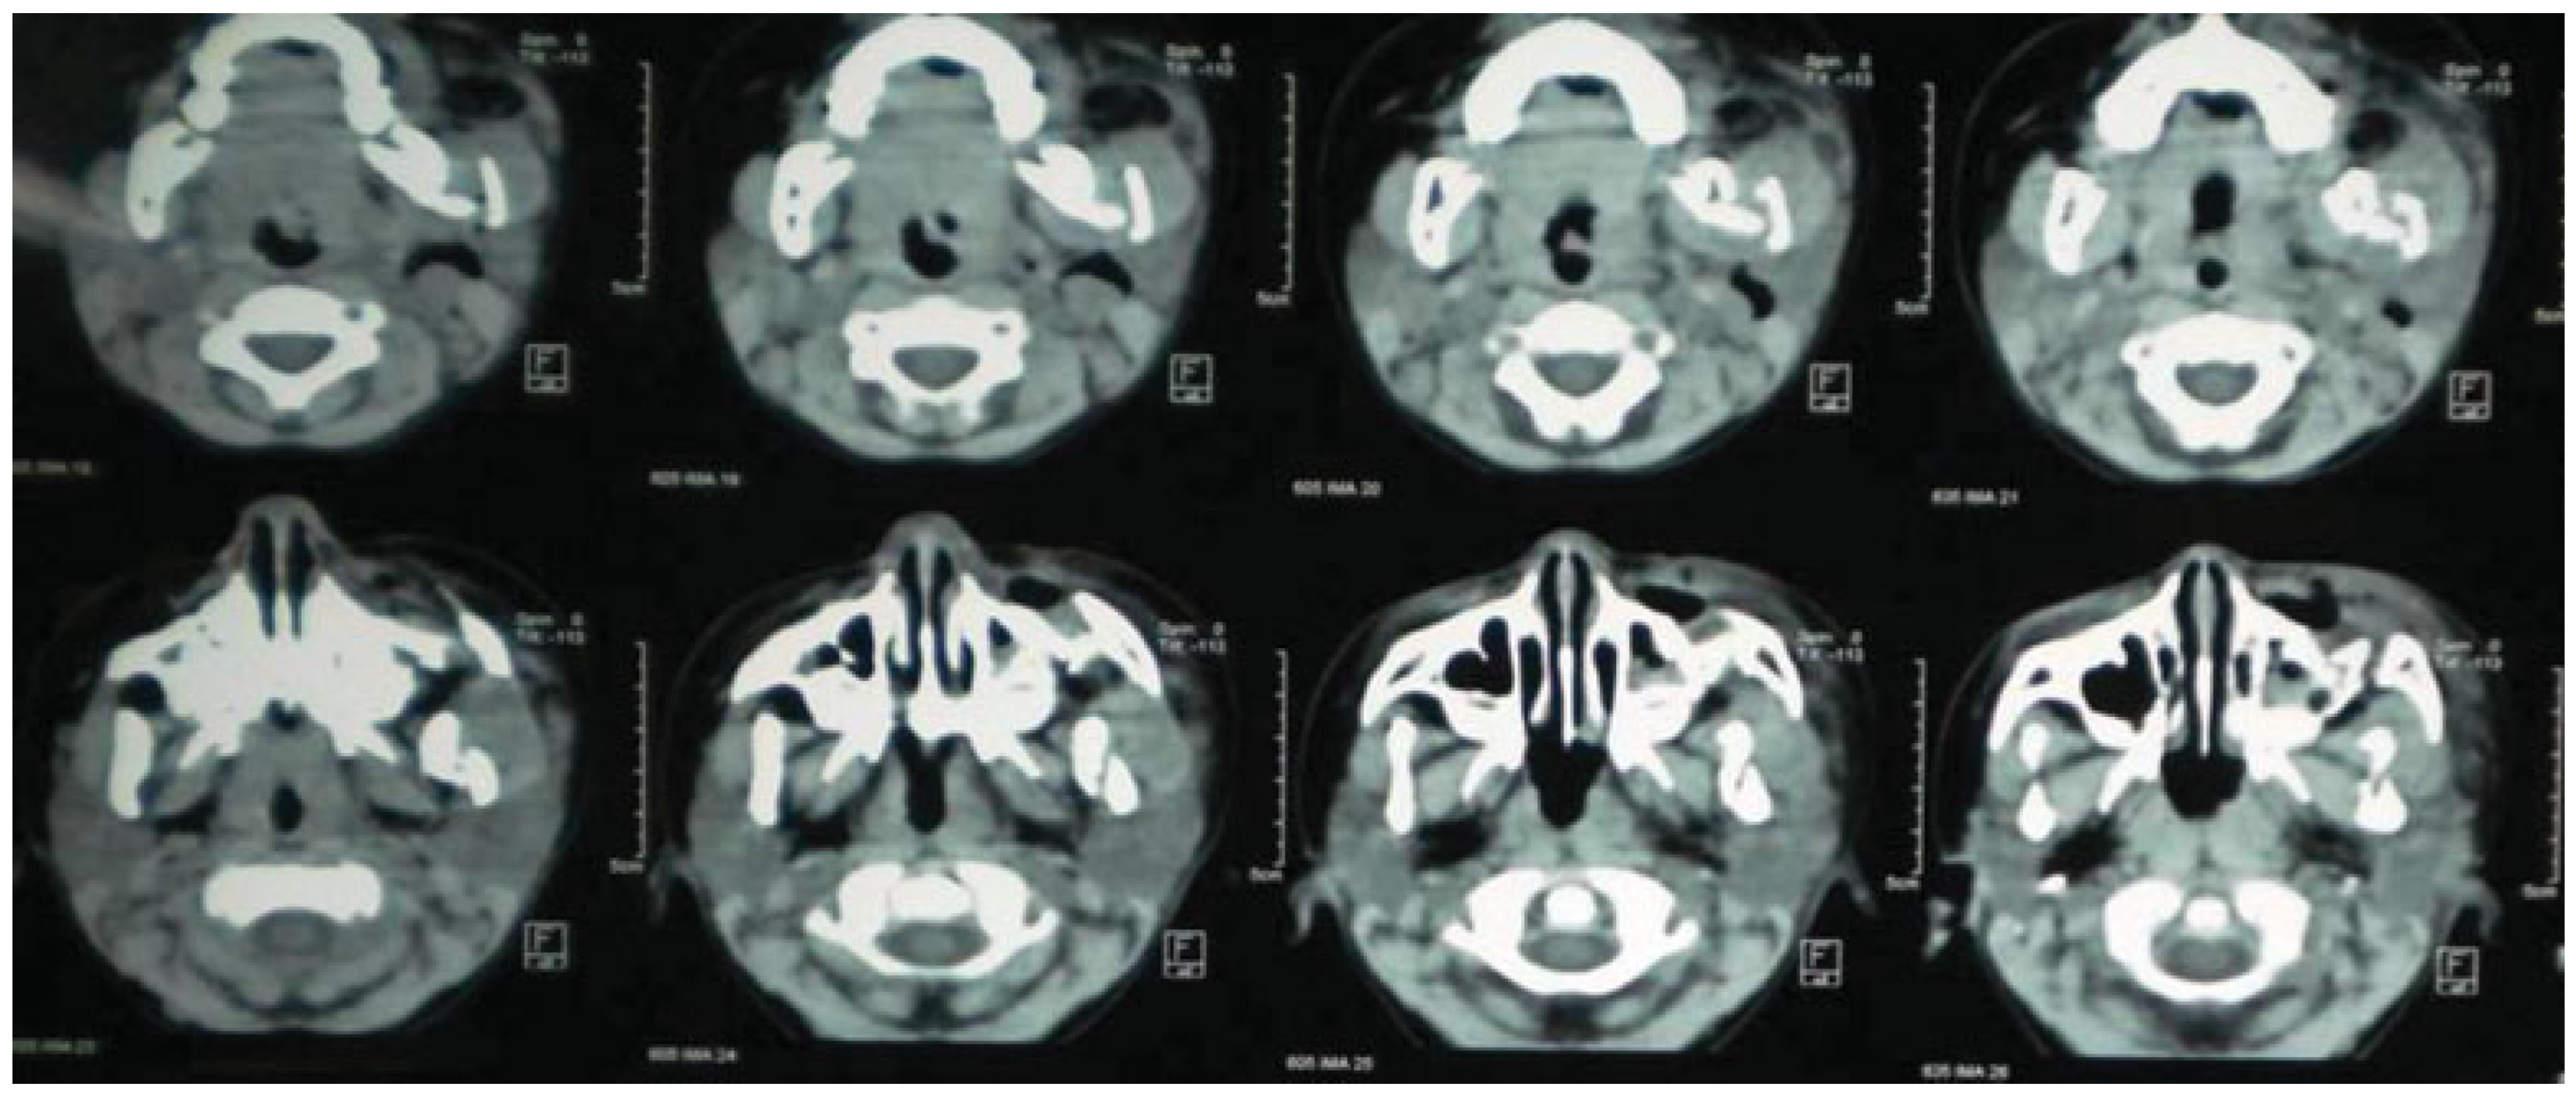

Mandible and Zygomatic Fracture in a 2-Year-Old Patient Due to Dog Bite

Case Report

Procedure